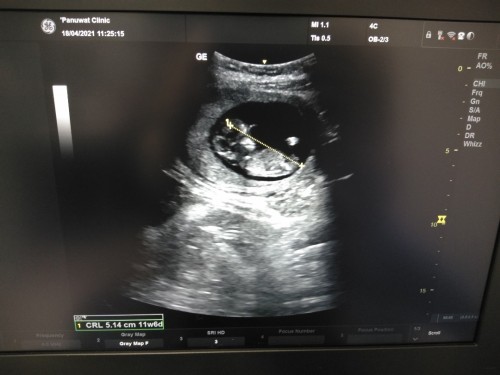

ซาวตอน11wค่ะ